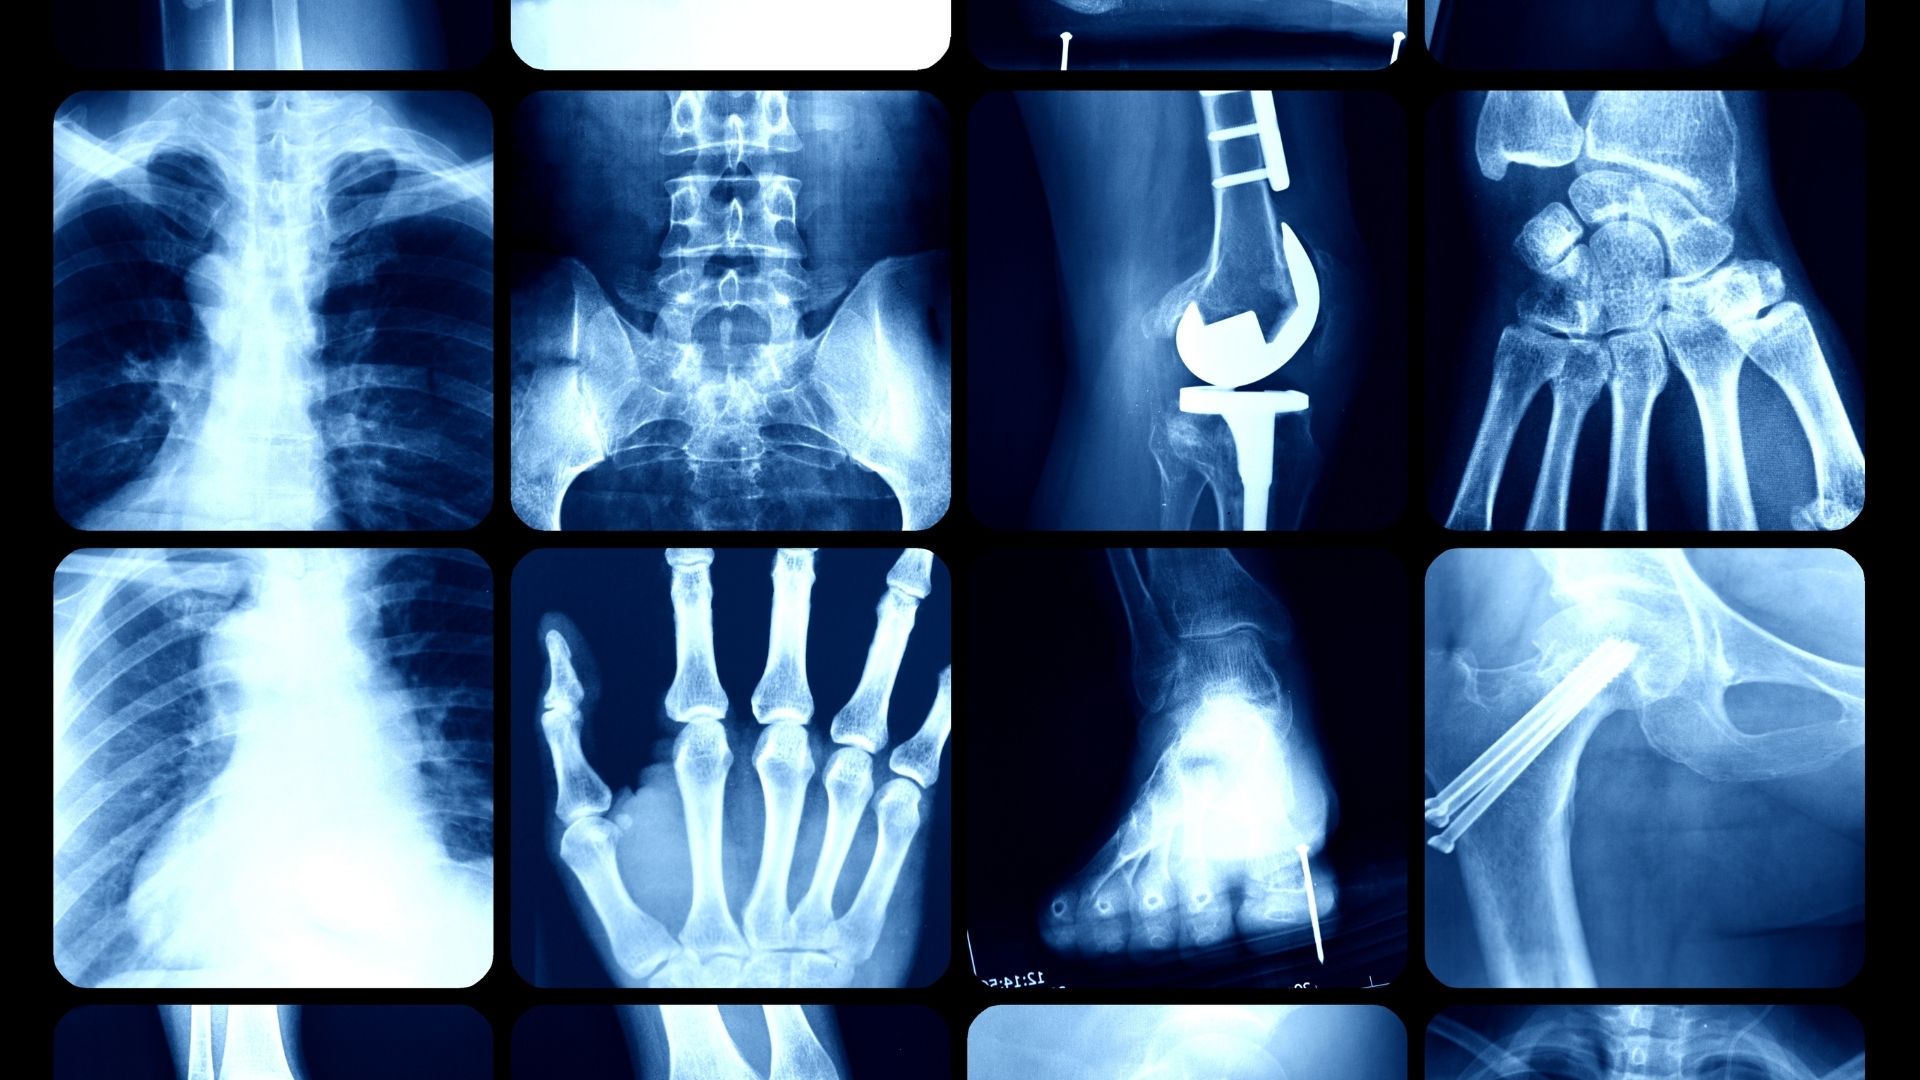

Trong quá trình khám chữa bệnh hiện nay, X-quang là một trong những phương pháp chẩn đoán hình ảnh được sử dụng phổ biến nhờ khả năng hỗ trợ bác sĩ quan sát cấu trúc bên trong cơ thể một cách nhanh chóng. Tuy nhiên, khi được chỉ định thực hiện, nhiều người không khỏi băn khoăn về chi phí vì mức giá có thể khác nhau giữa các cơ sở y tế, cũng như giữa chụp thường và chụp kỹ thuật số.

Đây là câu hỏi được nhiều người đặt ra đầu tiên khi có chỉ định chụp X-quang. Trên thực tế, không có một mức giá cố định áp dụng cho tất cả các trường hợp. Chi phí chụp X-quang hiện nay thường được xây dựng dựa trên loại kỹ thuật sử dụng, vị trí cần chụp và quy định giá của từng cơ sở y tế. Giá chụp X-quang nhìn chung nằm trong mức mà đa số người dân có thể tiếp cận, đặc biệt khi có bảo hiểm y tế.

Chụp X-quang thường là hình thức truyền thống, sử dụng phim X-quang để ghi nhận hình ảnh. Phương pháp này vẫn được áp dụng rộng rãi tại nhiều cơ sở y tế công lập. Mức giá của chụp X-quang thường tương đối thấp, phù hợp với những trường hợp cần kiểm tra cơ bản như gãy xương, trật khớp hoặc khảo sát nhanh tình trạng phổi. Giá chụp X-quang thường dao động trong khoảng vài chục nghìn đến hơn một trăm nghìn đồng cho mỗi vị trí chụp, tùy theo quy định cụ thể của từng đơn vị.

X-quang kỹ thuật số là hình thức hiện đại hơn, cho phép hiển thị hình ảnh trực tiếp trên máy tính với độ phân giải cao. Ưu điểm của phương pháp này là hình ảnh rõ nét, dễ lưu trữ và thuận tiện cho việc hội chẩn. Tuy nhiên, chi phí chụp X-quang kỹ thuật số thường cao hơn so với chụp X-quang thường. Mức giá cao hơn thông thường phản ánh chi phí đầu tư thiết bị và công nghệ. Dù vậy, nhiều người vẫn lựa chọn hình thức này vì tính tiện lợi và độ chính xác trong chẩn đoán.